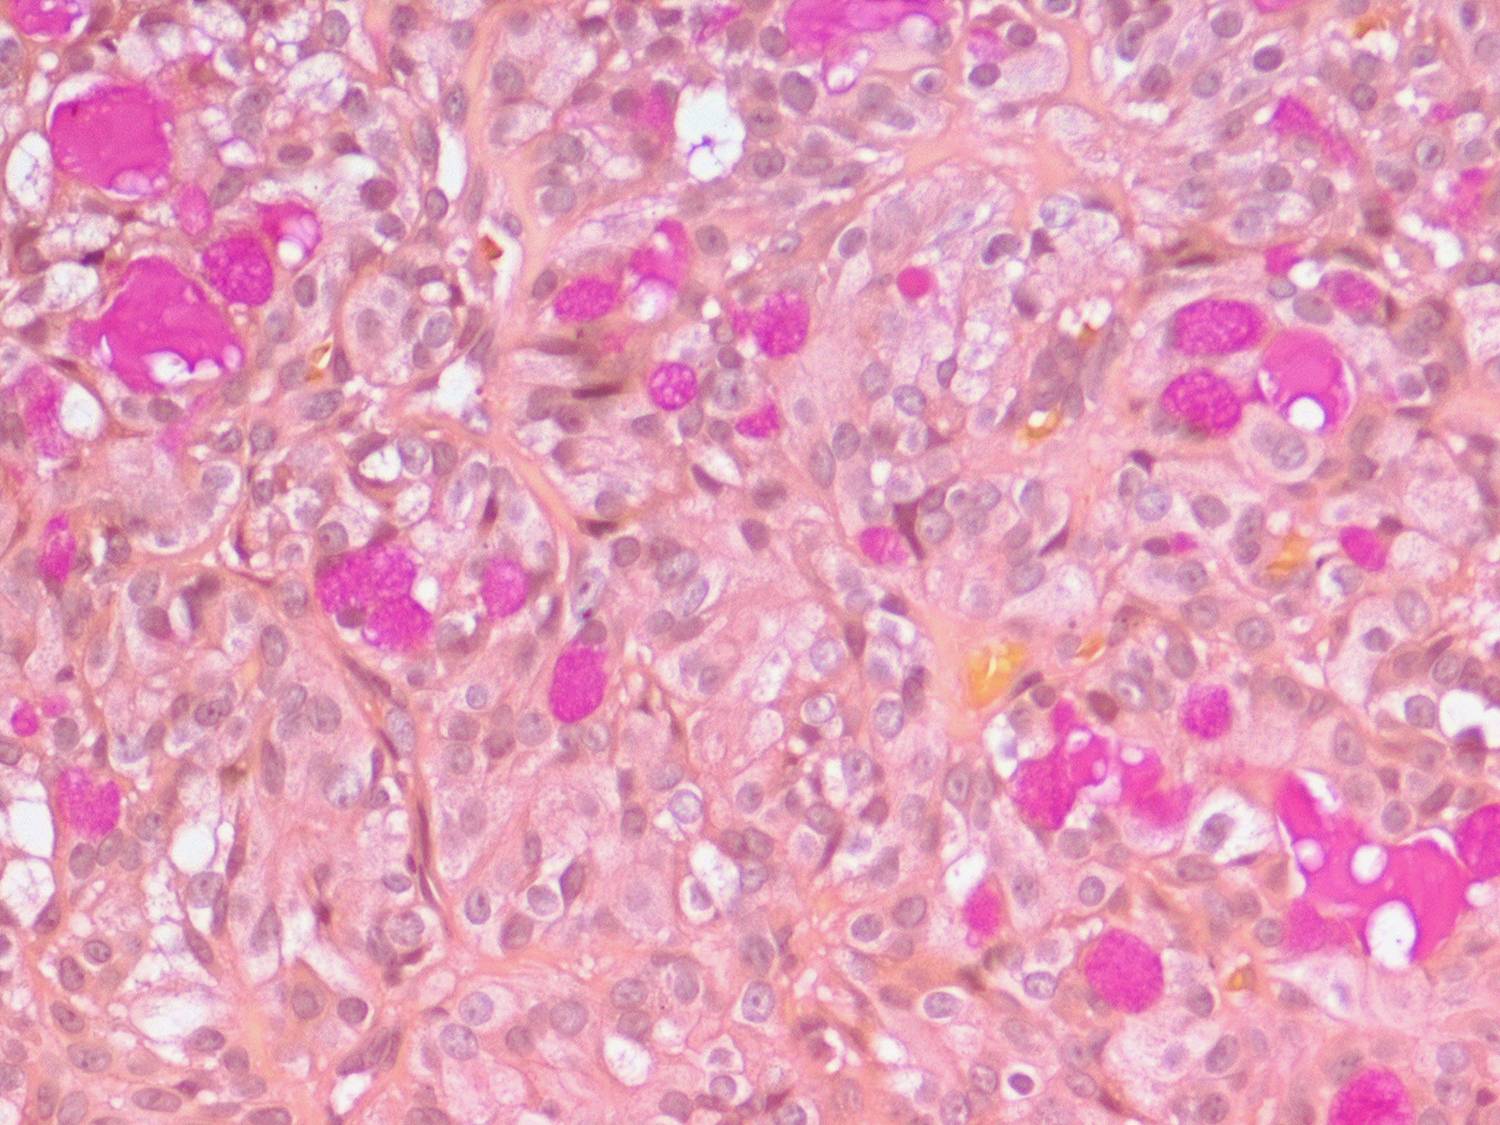

Mucoepidermoid carcinoma =الكارسينوما المخاطية البشروانية